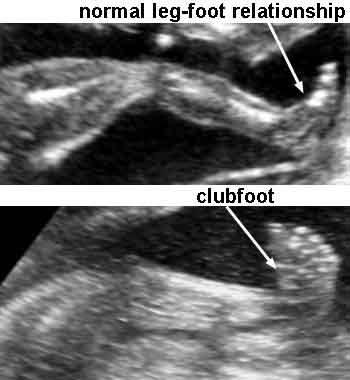

fetal ultrasound abnormalities abnormal anatomy sonography clubfoot foot medical scan weeks radiology leg diagnosis head normal limbs baby anomalies nursing